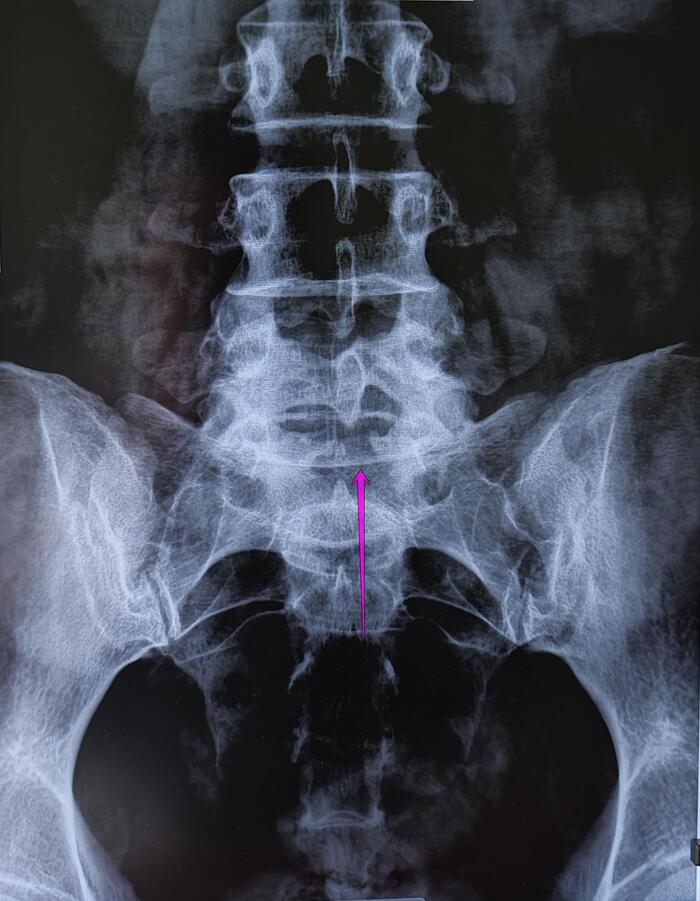

На Р-граммах грудного, поясничного отделов позвоночника определяется S -образное искривление оси позвоночника, с левосторонней дугой, вершиной на Th10,угол девиации 20 град., правосторонней дугой, вершиной на L2, углом девиации 15 град.

Итоговый диагноз: Патологический гиперкифоз грудного отдела позвоночника 4 ст. по Коббу. Клиновидная деформация тел Th6, Th7, Th8 позвонков, как следствие перенесенной остеохондропатии, соответствует болезни Шейермана-Мау.S-образный сколиоз 2ст.Остеохондроз грудного, поясничного отделов позвоночника.

В данном случае непризывные категории годности будут по сколиозу 2 ст(угол искривления более 18 град.)-ст.66в-В(ограниченно годен к в/сл), гиперкифозу грудного отдела позвоночника 4 ст, с клиновидной деформацией 3х позвонков грудного отдела как следствие остеохондропатии-ст.66а-Д(не годен к в/сл),иногда ставится 66в-В.